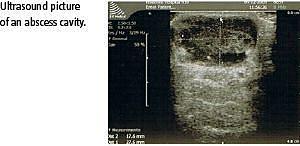

Subkutane abscesser er hyppigt forekommende, og standardbehandlingen består af incision med efterfølgende åbenstående sår eller incision, currettage og primær suturering under antibiotikadække. Ultralydvejledt drænage af abscesser i mammae kombineret med antibiotika har vist sig at være effektiv og er blevet standardbehandlingen af denne type abscesser. Formålet med dette studie var at afklare gennemførligheden af ultralydvejledt abscesdrænage kombineret med antibiotika i behandlingen af subkutane abscesser på truncus.

Ultralydvejledt drænage blev udført med en 18 G (1,2 mm) nål, og kaviteten blev efterfølgende skyllet med saltvand. Patienterne fik antibiotika i form af 1 g dicloxacillin og 0,5 g metronidazol tre gange dagligt i ti dage. Dyrkning og resistensbestemmelse fra abscesmaterialet blev anvendt til justering af antibiotikabehandlingen. Opfølgende kontrol blev foretaget med 3-6-dagesintervaller, og ved restabsces blev proceduren gentaget. Ved manglende bedring efter to behandlinger blev der foretaget incision. Opfølgning blev foretaget efter minimum en måned. Succesfuld behandling blev defineret som ophævelse af kliniske tegn på absces samt obliteration af absceskavitet.

Medianalderen for patienterne var 35 år, og 78% havde tidligere haft en eller flere abscesser. Mediantiden fra symptomdebut til behandling var fire dage. Medianabscesstørrelsen opmålt med ultralyd (kaviteten) var 20 mm. Bedring i symptomerne blev rapporteret af 89% af patienterne ved første kontrolbesøg. Behandlingen var initialt succesfuld hos 25 af de 27 patienter (93%). Af de 25 patienter, der opnåede succes, fik 12 patienter foretaget en, 12 patienter to og en patient tre tømninger. Mediantiden fra første behandling til sidste kontrol var ni dage. Efter en medianopfølgningstid på 84 dage havde seks (24%) patienter haft recidiv af abscessen. Med hensyn til tilfredshed angav 22 af 27 patienter (81%), at de var tilfredse eller meget tilfredse med behandlingen, og 24 af 27 patienter (85%) ville anbefale behandlingen til andre patienter med subkutane abscesser.